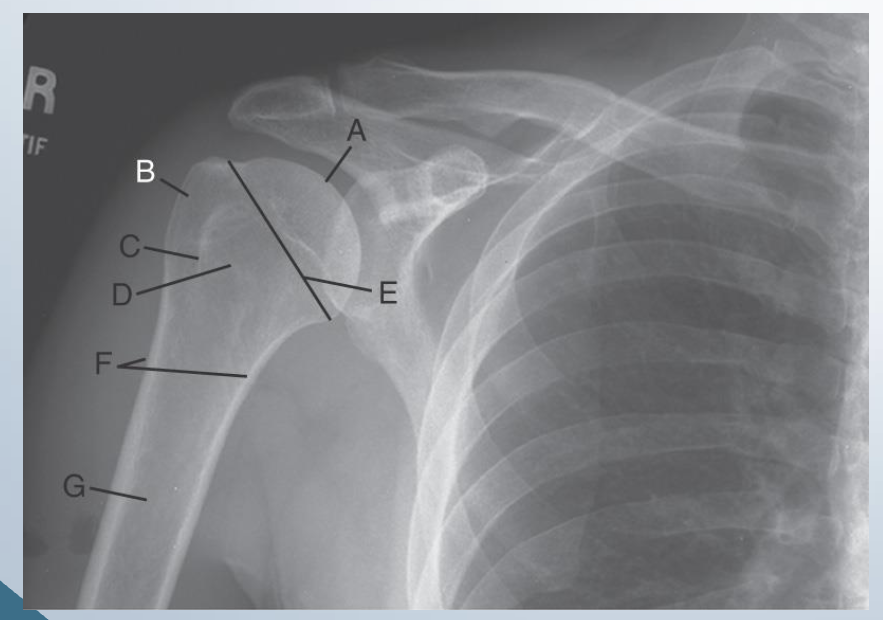

AP external rotation

LABEL

A. Head of humerus

B. Greater Tubercule

C. Intertubercular sulcus

D. Lesser tubercule

E. Anatomic neck

F. Surgical neck

G. Body